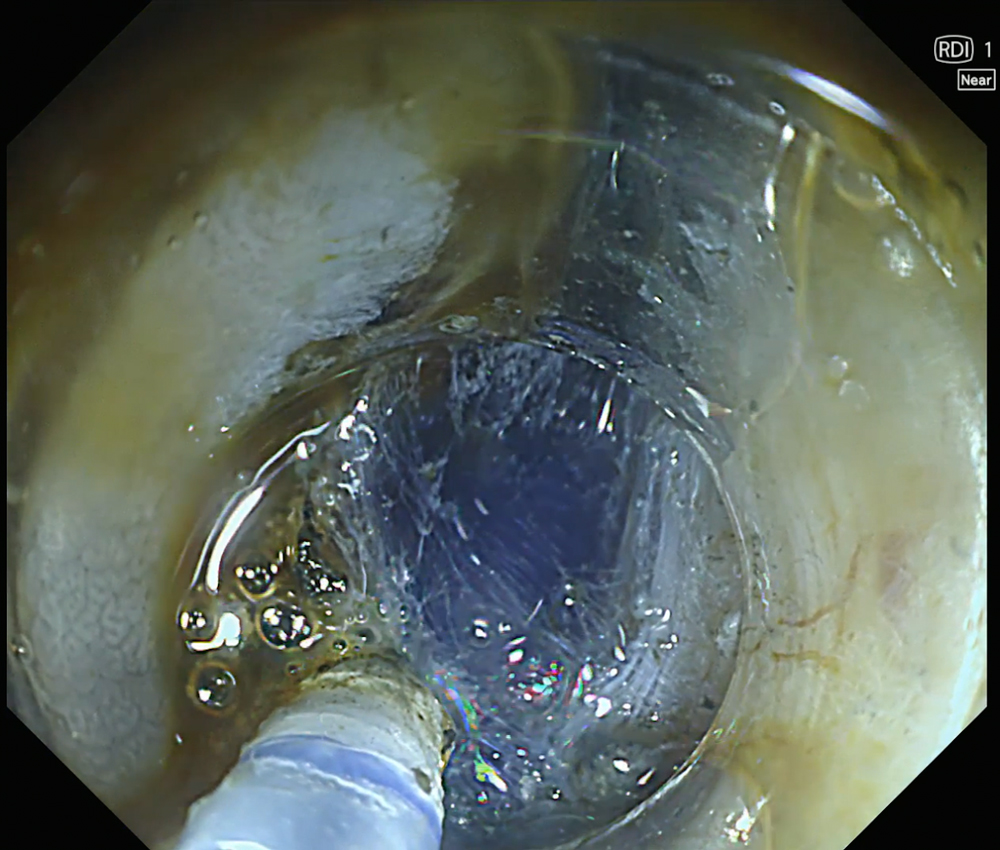

13. Submucosal layer visualization with RDI Mode 1

In RDI mode 1, indigo carmine enhances visualization of the submucosal layer during ESD, allowing clearer identification of the cutting line and facilitating controlled dissection.